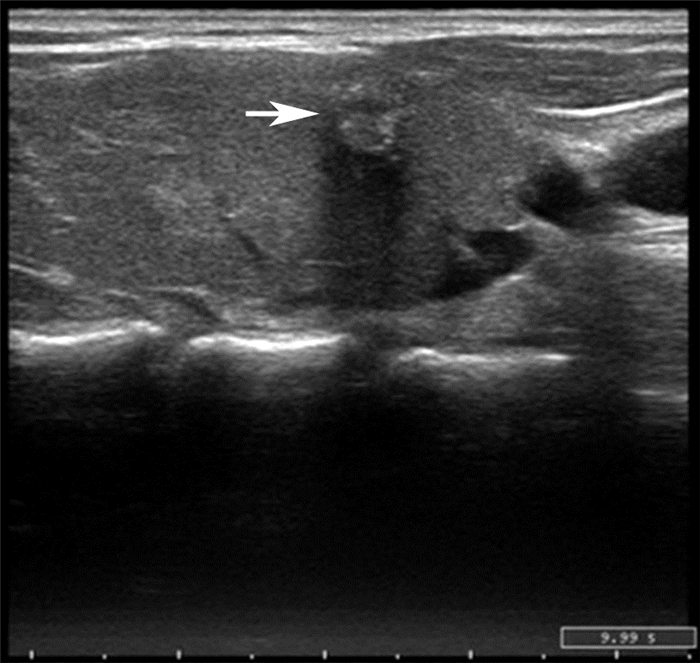

二、PTC患者BRAF突变与超声图像特征分析BRAF突变阳性病例的PTC病灶在形态、边界、边缘、钙化、内部回声等方面, 与BRAF突变阴性病例比较差异均无统计学意义(P均>0.05), 见图 1~3、表 1。

图 1 一例PTC患者甲状腺右侧叶超声图 箭头所示为肿块,显示病灶为极低回声、纵横比>1、形态不规则、边界不清、内部可见微钙化,局部甲状腺包膜中断 |